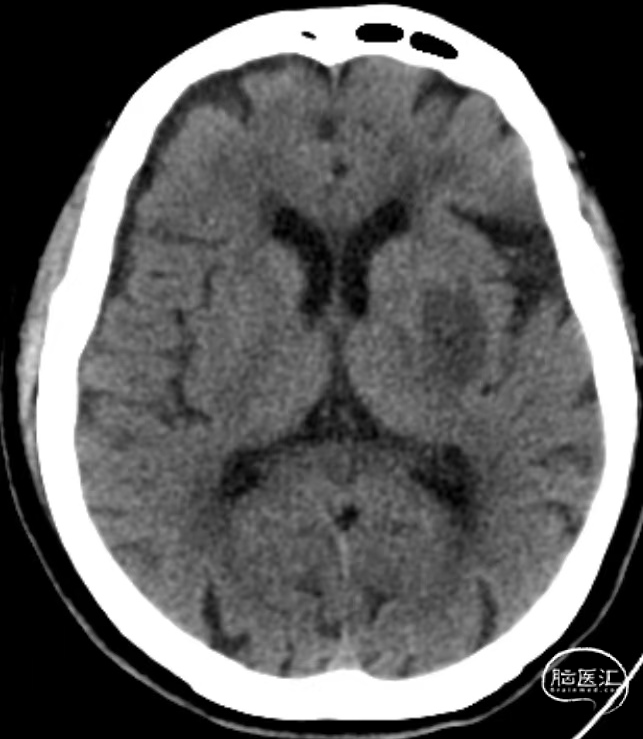

术前MRI

术前MRA:左侧大脑中动脉闭塞。